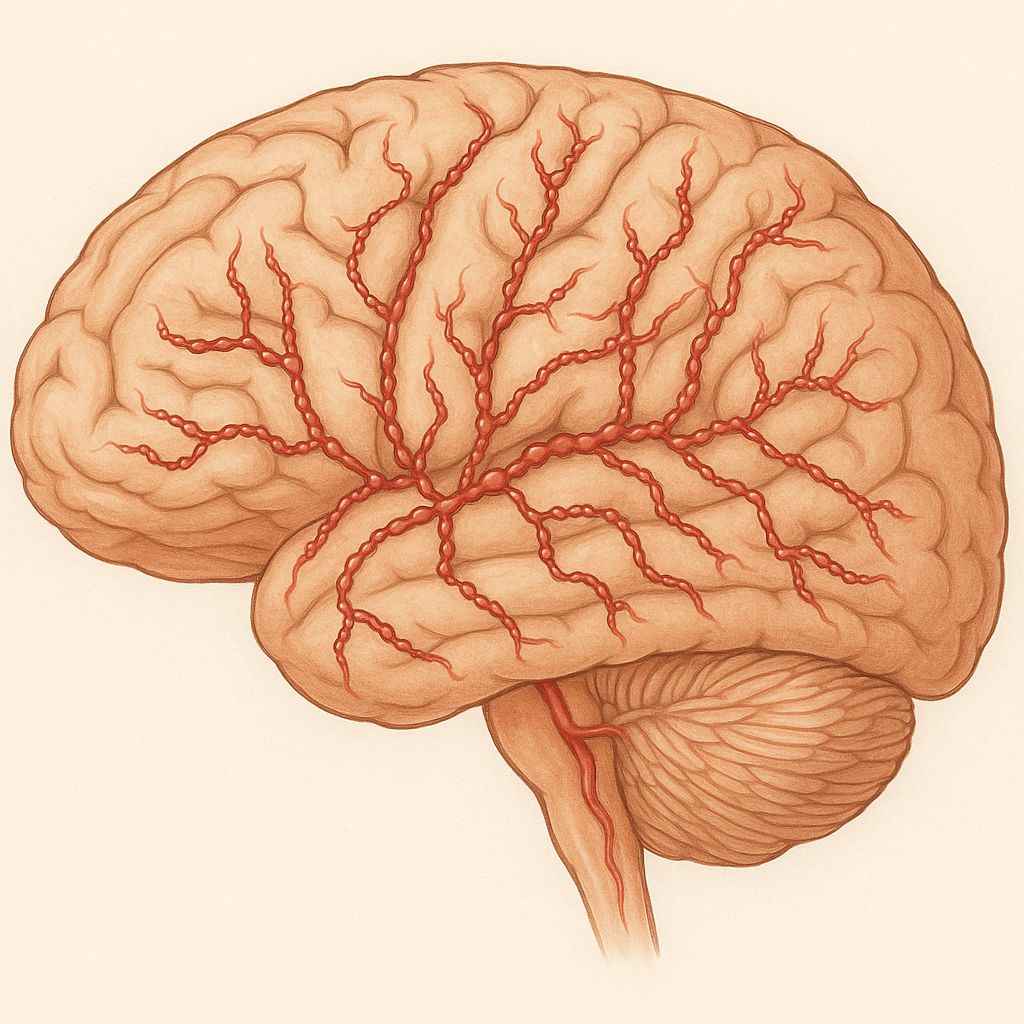

Cortical spreading depression generates aura and activates brainstem nuclei (dorsal pons), which in turn excite the trigeminovascular system.

Trigeminal afferents release CGRP, substance P, and neurokinin A, producing vasodilation, plasma extravasation, and neurogenic inflammation.

Central sensitization within the trigeminal nucleus caudalis and thalamus explains cutaneous allodynia and photophobia.

Hormonal fluctuations, genetic ion-channel variants (CACNA1A, SCN1A), and environmental triggers modulate neuronal excitability.

CGRP monoclonal antibodies and gepants directly target this pathway, validating the mechanistic model.